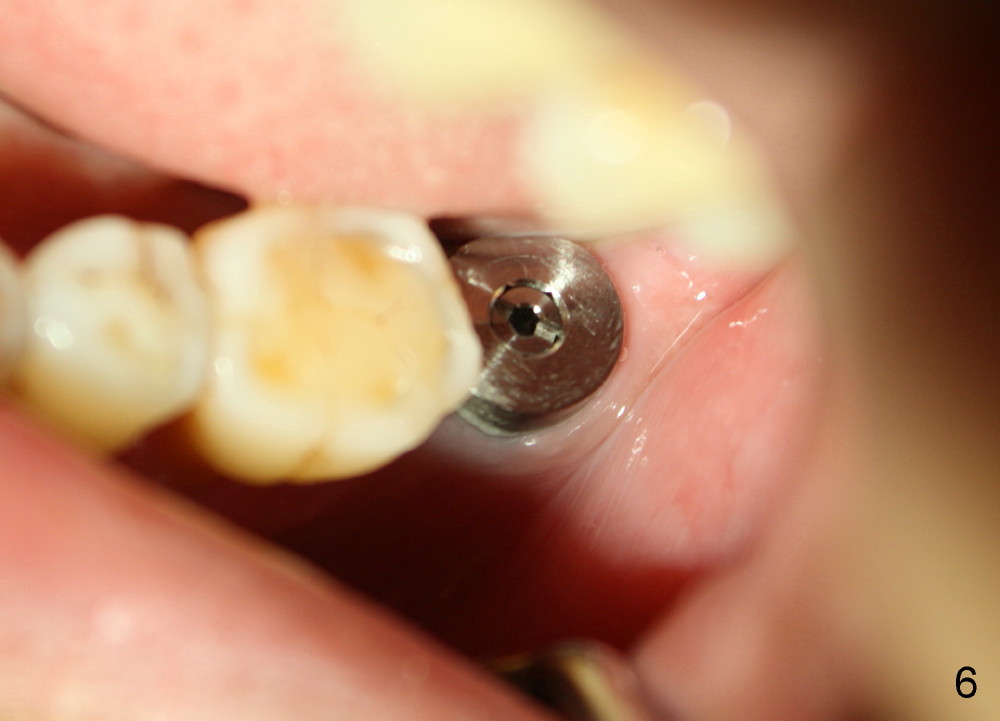

In contrast, the patient is asymptomatic after the 2nd placement. The implant remains stable (Fig.6 (15 days postop); Fig.7 (4 months postop)).